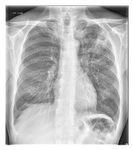

Opacificación aumentada de la región perihiliar derecha y del segmento superior de los lóbulos inferior y superior derechos coincidente con empeoramiento de neumonía por aspiración

De la colección del Dr. Roy Hammond. Usado con autorización